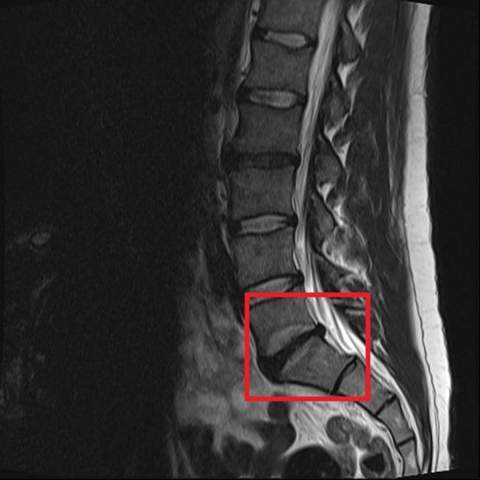

Bei Verdacht auf einen Bandscheibenvorfall sollte unbedingt ein Neurologe Neurochirurg oder Orthopäde aufgesucht werden damit dieser die weitere Diagnostik veranlasst und die entsprechende Therapie einleitet. Der zuständige Facharzt ist ein Orthopäde ein Neurologe oder ein Neurochirurg. Behandlung des Bandscheibenvorfalls Konnte durch das bildgebende Verfahren der Bandscheibenvorfall eindeutig diagnostiziert werden ist der genaue Sitz der Schädigung bekannt.

Beide bildgebenden Verfahren müssen individuell vom Arzt beurteilt und anschließend zur Diagnostik bei einem Bandscheibenvorfall verordnet werden. Was der Arzt untersucht. Hier sollten Patienten diese Hilfe zur Selbsthilfe einfordern.